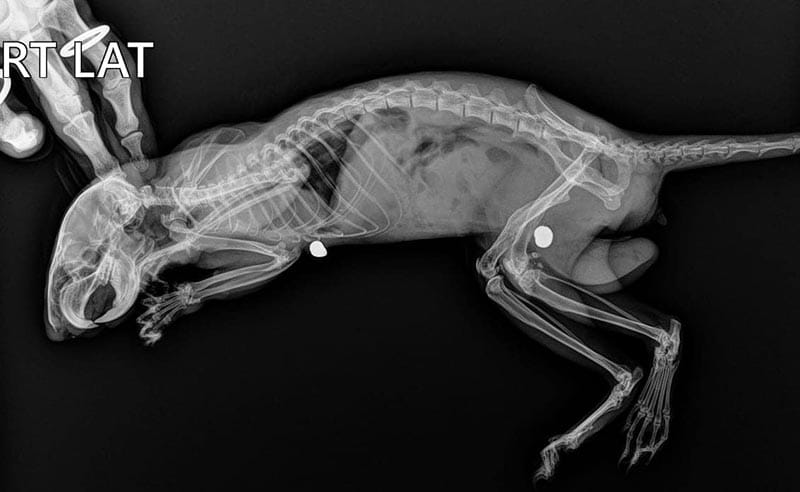

El cuerpo presentaba pérdida de fuerza y problemas respiratorios, en las placas se observó que le fueron disparados dos diábolos los cuales ya tenían tiempo en su organismo, sus huesos femorales estaban afectados así como su cadera.

En un procedimiento se los retiraron y detectaron que eran de plomo y generan intoxicaciones, por lo que el animalito estaba en tratamiento.